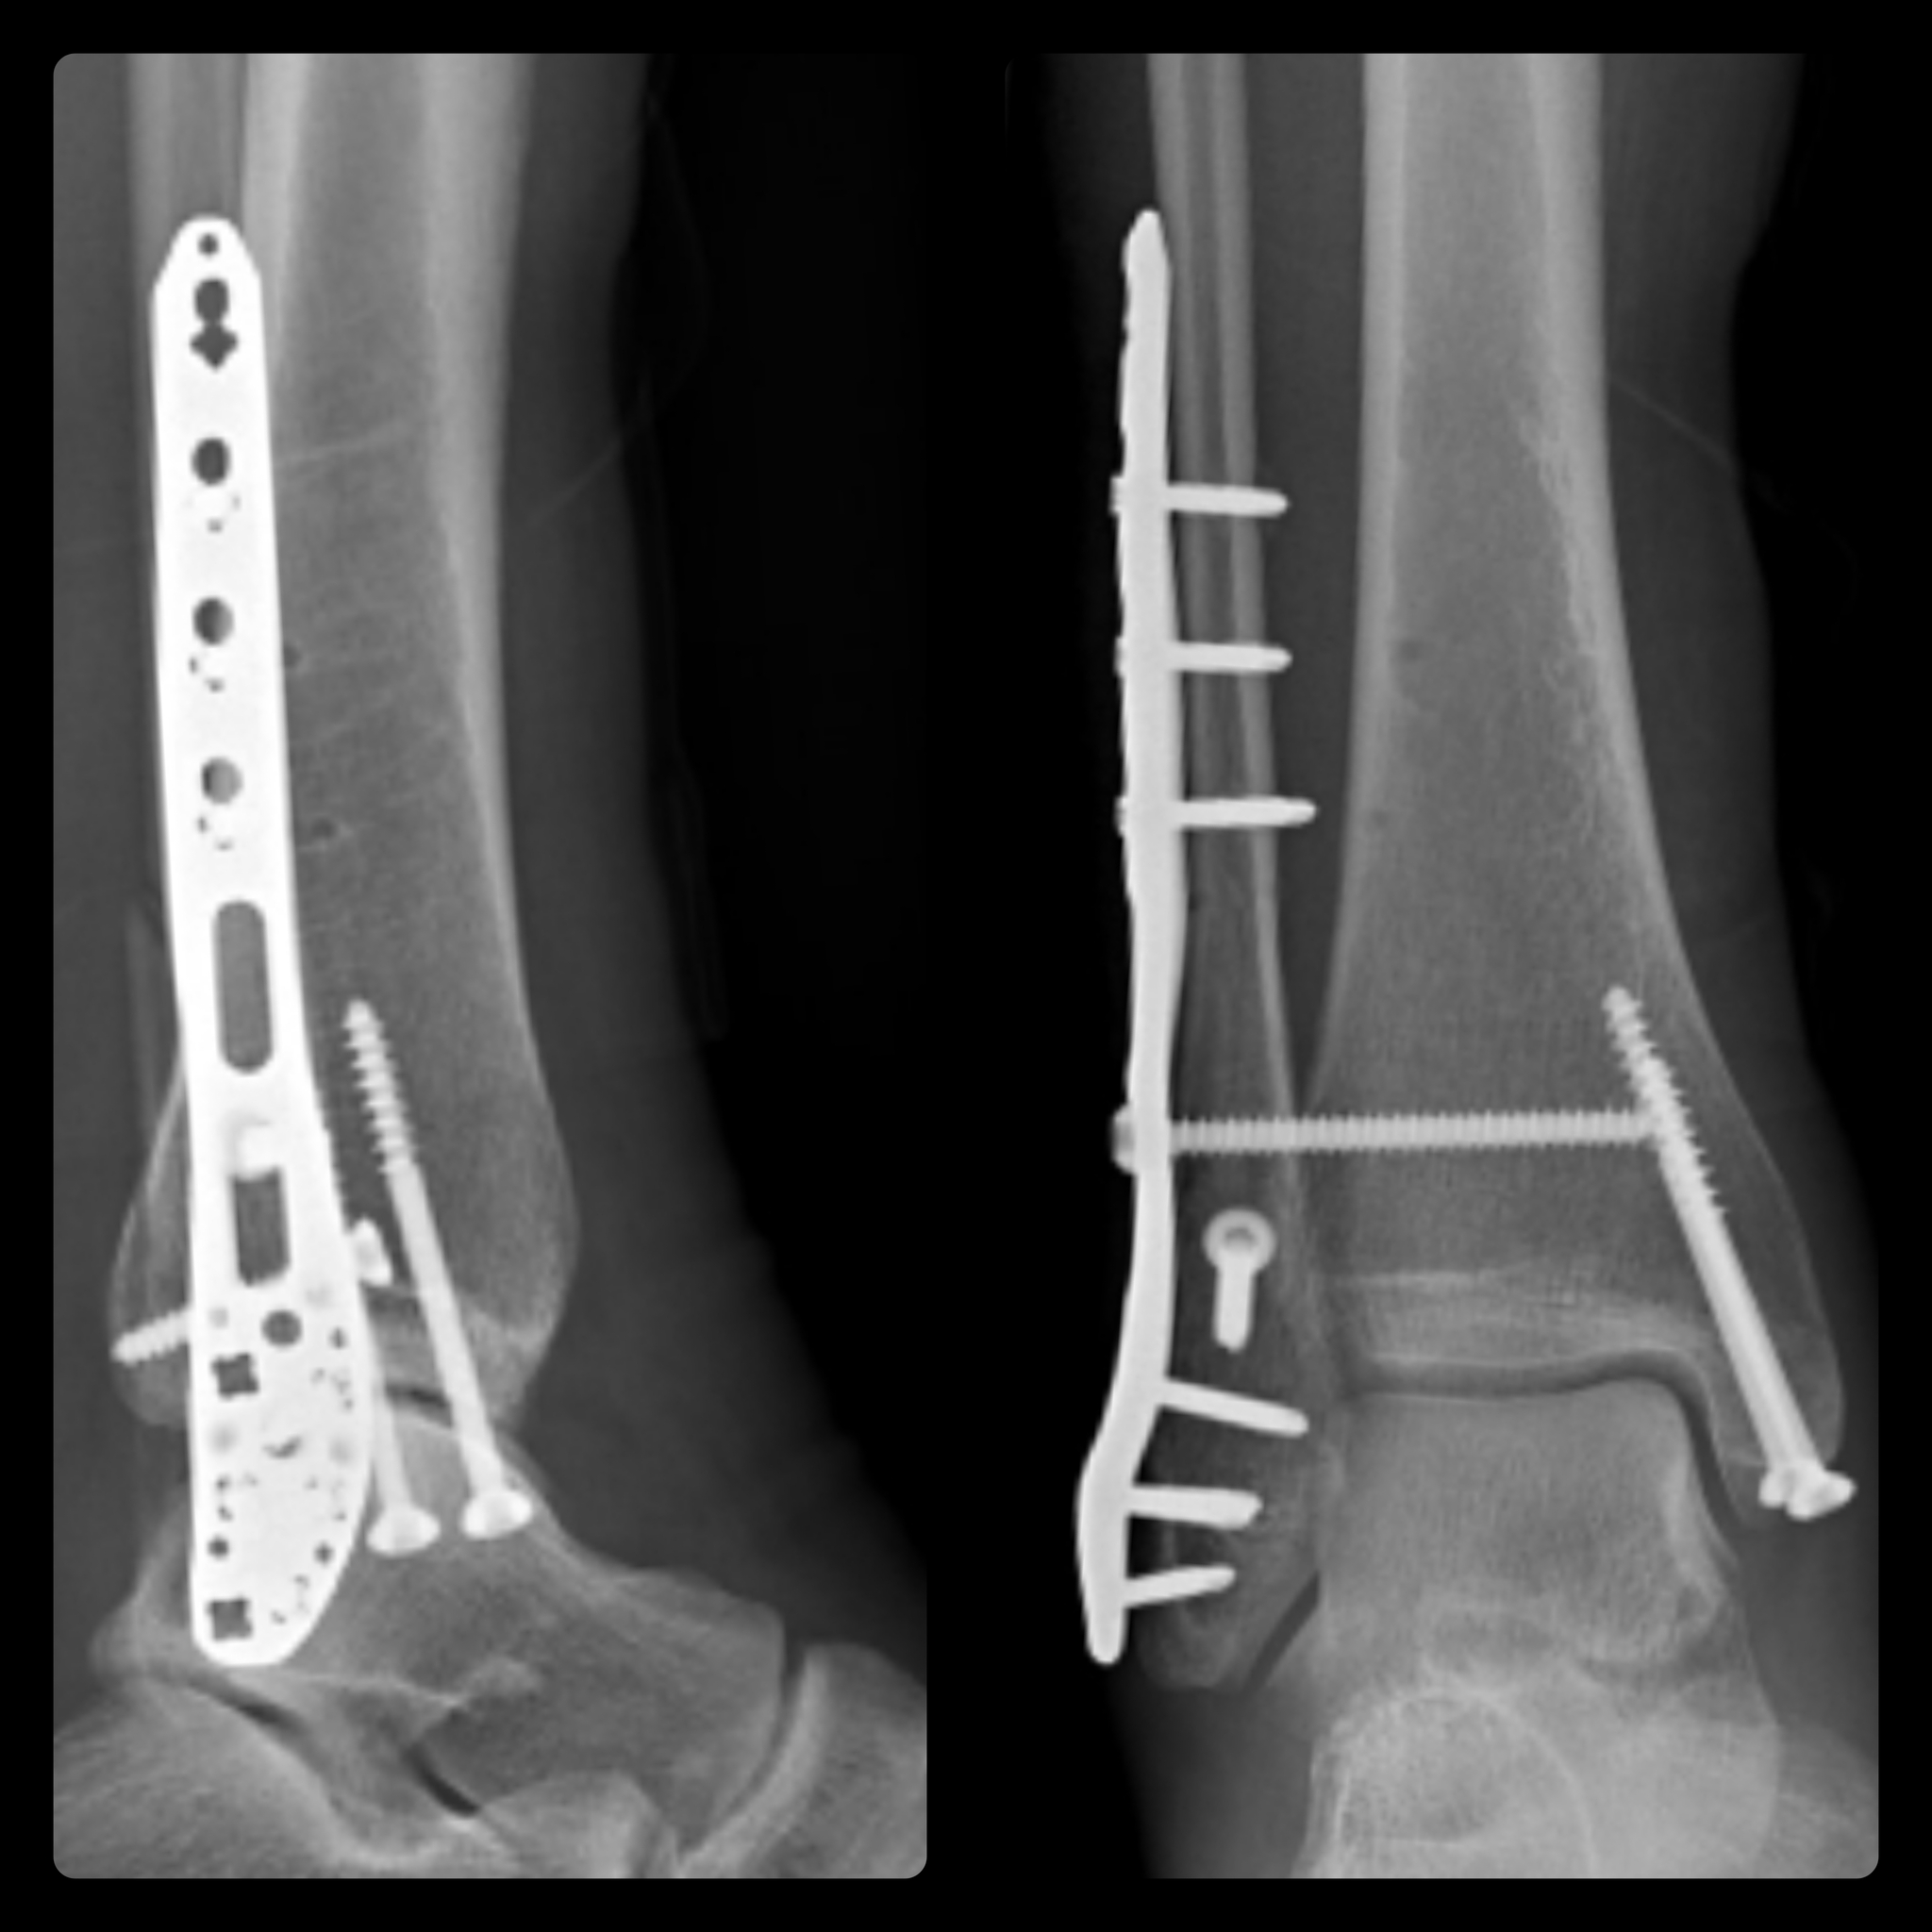

Интересно, у меня тоже левая нога, 2 пластины на МБК и ББК, ходил недели 3 на iwalk, потом на двух подмышечных костылях, потом на одном, сейчас трость, пытаюсь ходить без неё, тоже могу начать прогулку без трости, потом в конце приходится помогать.

Тоже дорсифлексия в течении дня плавает, то колено за носок, то нет. Он атрофии спасаюсь велотренажером, сейчас буду ходить в бассейн.

Вряд ли Вам при таких сроках уже разрешили полноценную нагрузку на стопу (либо это произошло сравнительно недавно). А всякие ЛФК и растяжки - штука безусловно важная (чтобы предотвратить контрактуры), но скорее всего недостаточная для полного восстановления.

По моему опыту, после возвращения к привычному уровню активности прогресс будет заметнее.